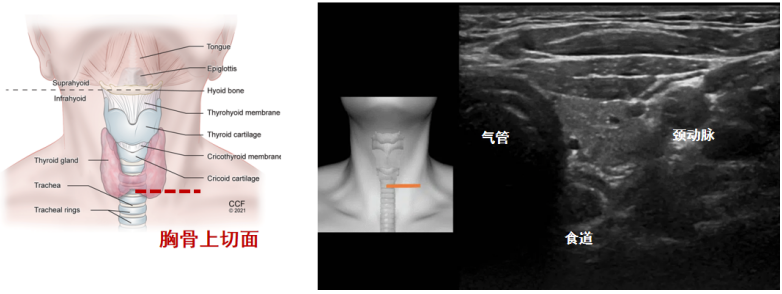

(6)胸骨上切面全景:目前有一些比较先进的超声设备可以将从左到右扫查的所有图像拼接为一张全景图(图15),我们可以看到两侧的胸锁乳突肌、颈内静脉、颈动脉、甲状腺、气管。与气管紧邻的是食管,位于气道的左后方。

图片

图15  胸骨上切面全景

我们将探头置于第二、三软骨环或胸骨上切迹靠近气道左侧处,就可以看到一个典型的倒三角形结构,分别由气管、颈动脉和食组成(图16)。在此切面下,我们可以直接观察插管的位置,是在气管内还是在食内。

图16  胸骨上切面